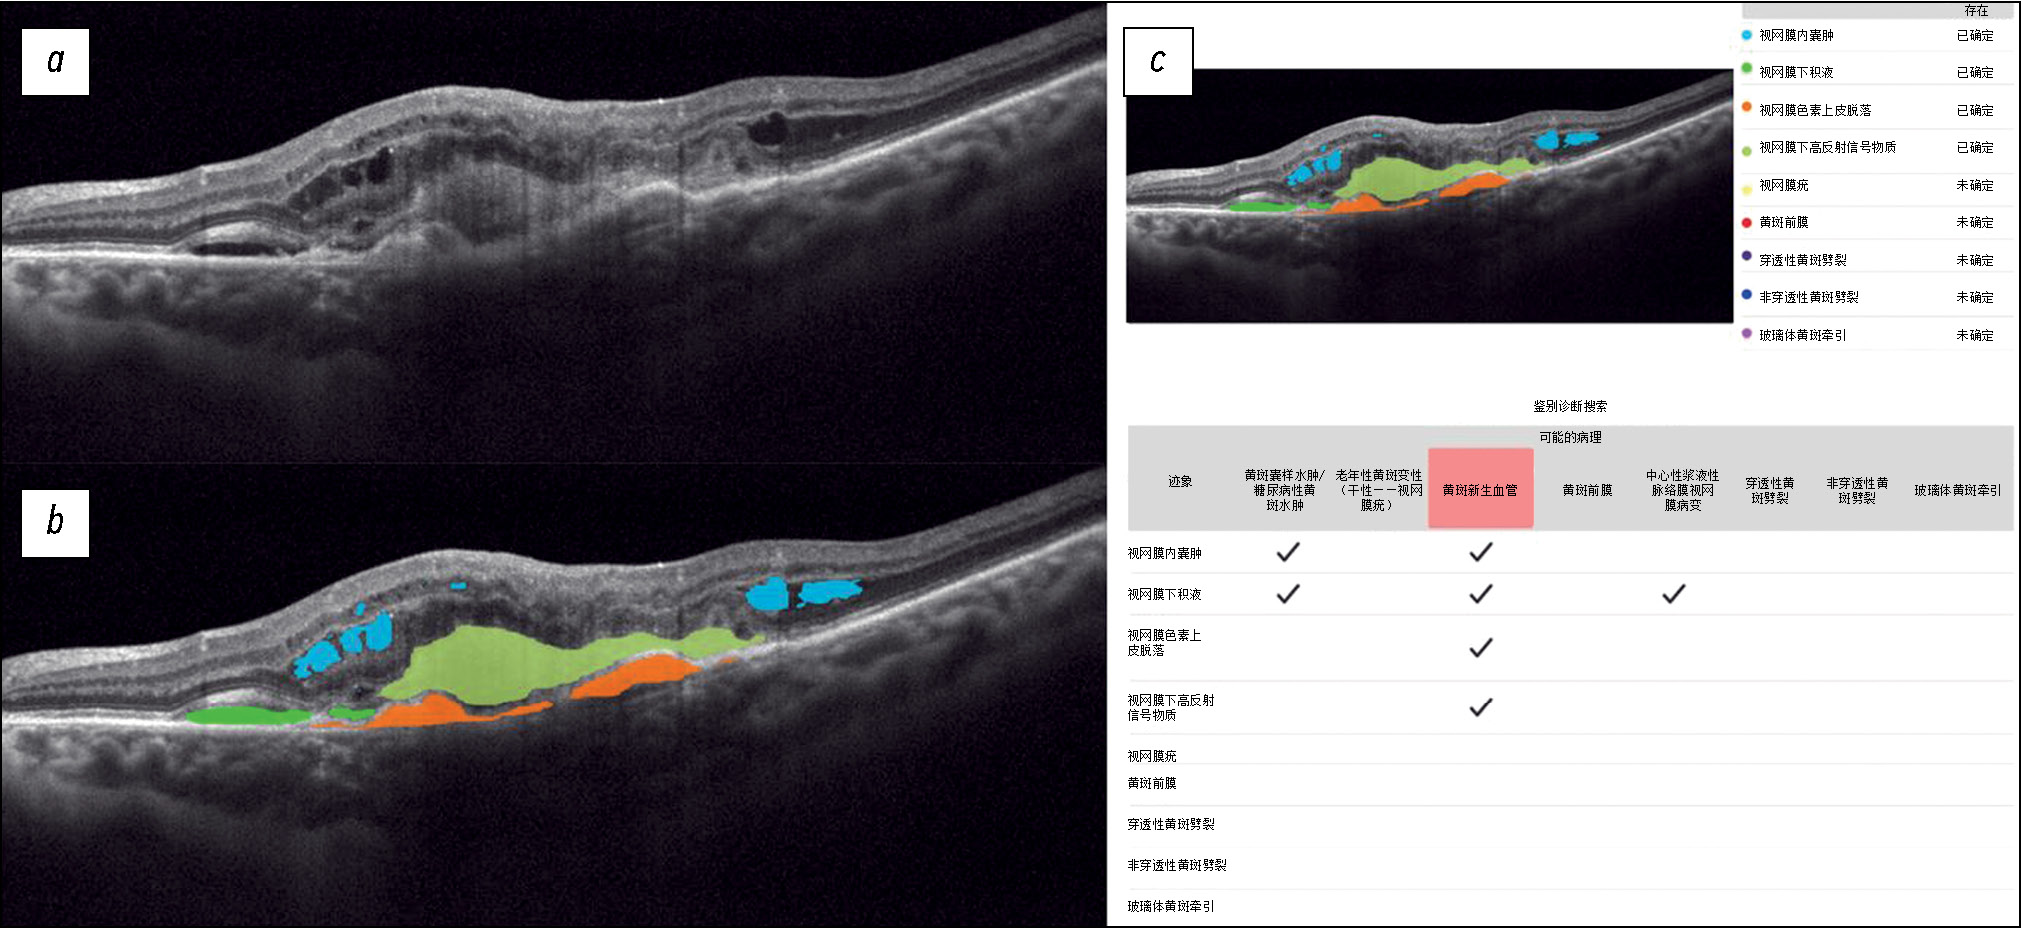

Fig. 3 shows a structural OCT scan of the macular zone of patient K (69 years old) with a full-thickness macular hole diagnosed by an ophthalmologist. In the analysis of the structural OCT scan by Retina.AI, the algorithm segmented the following pathological signs: full-thickness macular hole, intraretinal cysts, and epiretinal membrane. The program report registered a full-thickness macular hole and epiretinal membrane.

Fig. 3. An example of the optical coherence tomography scan analysis of a patient with macular hole, epiretinal membrane by the artificial intelligence algorithm: a — structural optical coherence tomography scan; b — optical coherence tomography scan after segmentation of the pathological features (macular hole — violet mask, intraretinal cysts — blue masks, epiretinal membrane — red masks); c — scan analysis report (the reporting table of the differential diagnostic search, probable pathology is highlighted in red — macular hole, epiretinal membrane).